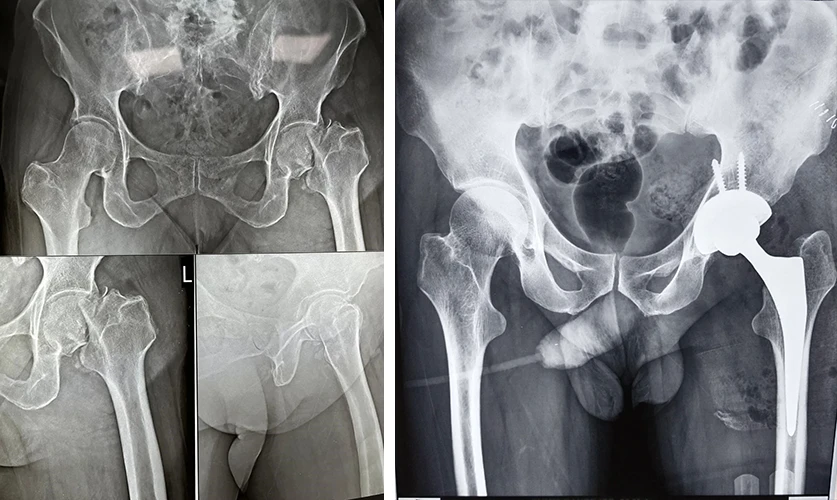

Total Hip Replacement

Are your hips causing you constant discomfort? If you're tired of living with hip pain, Dr. Prasun Sanyal is your best solution.